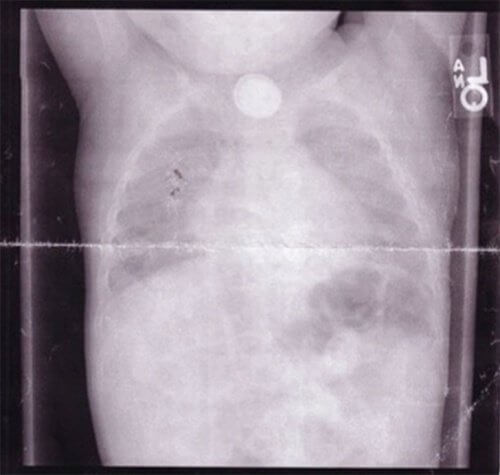

Tornati al pronto soccorso, in seguito ad un sintomo così poco comune, i medici lo sottoposero ad alcune analisi più dettagliate e, tramite una radiografia al torace, capirono cosa stava compromettendo la sua salute: una batteria a bottone.